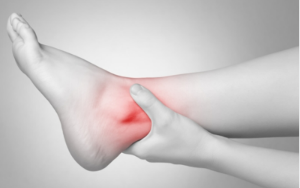

3. 통풍 증상 - 부종

육안으로 보일 만큼 해당 부위가 크게 붓는 경우가 많습니다. 특히나 발의 경우는 신발이 들어가기 않을 만큼 붓기도 합니다.